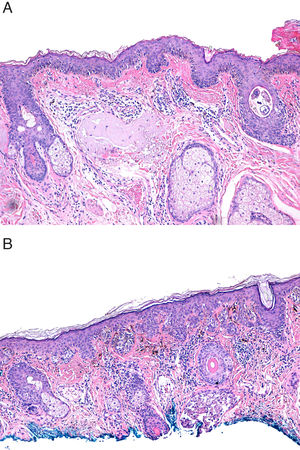

The 4th edition of the World Health Organization (WHO) Classification of Skin Tumors, published in 2018, reclassified superficial spreading melanomas (SSMs) as low-CSD melanomas and lentigo maligna melanomas (LMMs) as high-CSD melanomas.1,2 High-CSD is defined by the histological observation of severe (grade III) solar elastosis (SE) in the dermis of the surrounding healthy skin around the cutaneous melanoma (CM).1–3 Grade III SE is described by the presence of homogeneous clumps of elastotic material that have lost their texture of individual fibrils2 (Fig. 1A). In turn, low-CSD is the absence of SE, or the presence of mild (grade I [Fig. 1B]) or moderate (grade II) SE. Thus, the grade of SE became a major criterion to distinguish between these two types of CM.